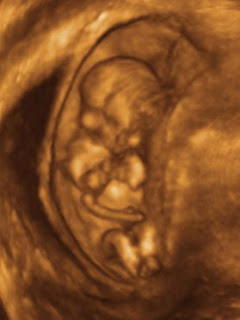

Your baby’s organs have been finished forming for a long time. Now is the time for finishing touches. The lungs make final preparations for birth. Your baby’s kidneys are still producing lots of urine every day.

While your baby may be putting on half a pound a week up until about week 37 at which point weight gain slows drastically. The average birth weight is still about seven and a half pounds. Your baby will measure between 18-22 inches at birth.